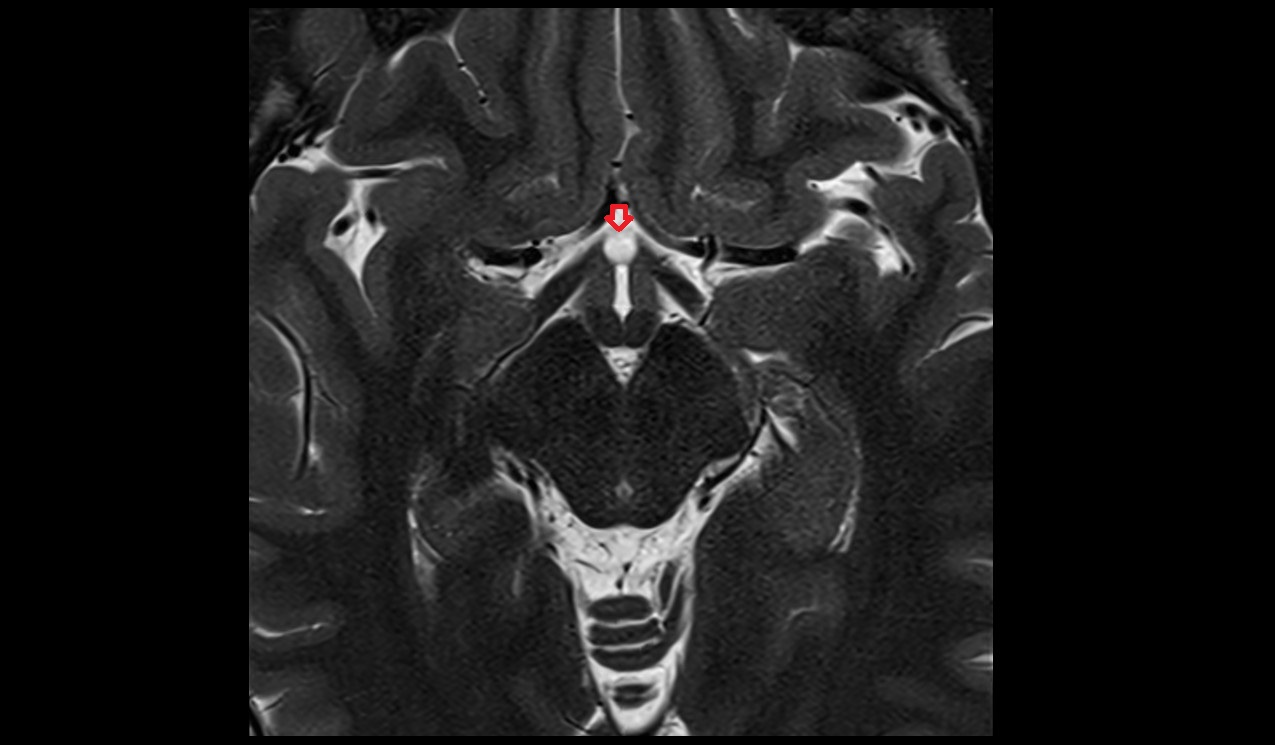

- Pituitary stalk